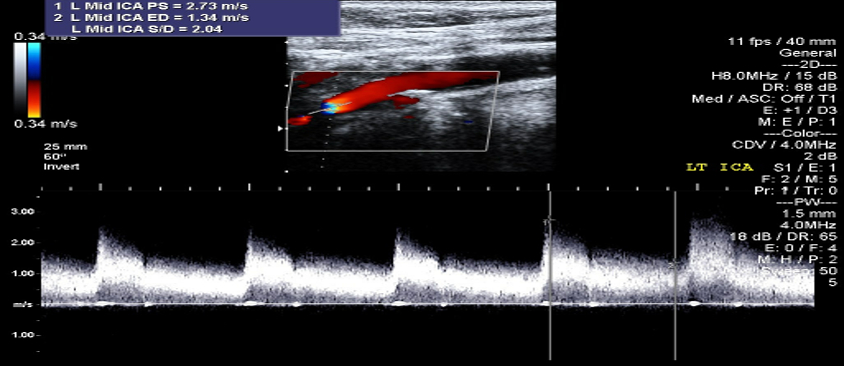

An 80-year-old woman with well-controlled hypertension presented with new-onset labile systolic pressures ranging from 90 to 200 mmHg. At age 63, she received radiation for SCC of the tongue. Eight years later, she developed episodic headaches and paresthesias during hypertensive spikes. Cardiology workup revealed persistent BP variability (see Figure 1), inappropriate heart rate responses, and sensitivity to antihypertensives—leading to hypotensive episodes. Carotid angiography showed 85% stenosis of the right ICA, successfully stented. A decade later, she had significant left-sided carotid disease (Figures 2a and 2b). Despite interventions, she continued to have erratic BP fluctuations and recurrent syncopal episodes. Radiation-induced baroreflex failure was suspected based on her clinical course and history.